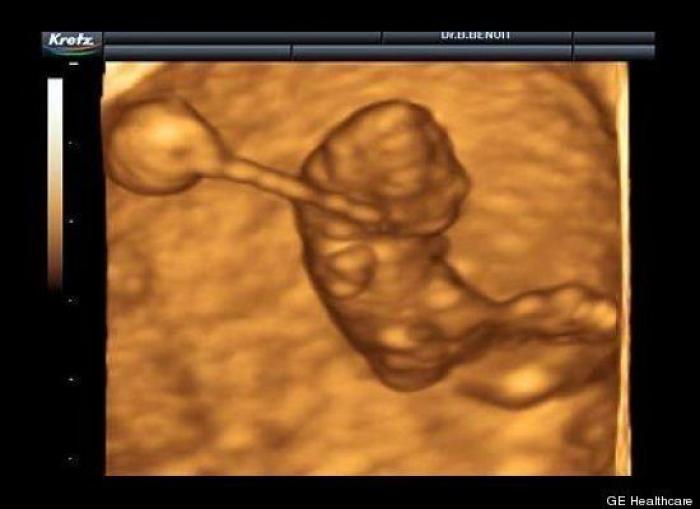

En esta galería puedes ver en fotos como es el desarrollo de un feto de semana en semana:

Desarrollo del feto, en fotos